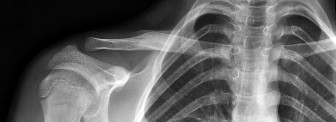

A 12-year-old elite Little League pitcher complains of progressively worsening pain in his throwing shoulder during the late cocking phase. Radiographs show widening and sclerosis of the proximal humeral physis. What is the primary pathophysiology of this condition (Little League Shoulder)?